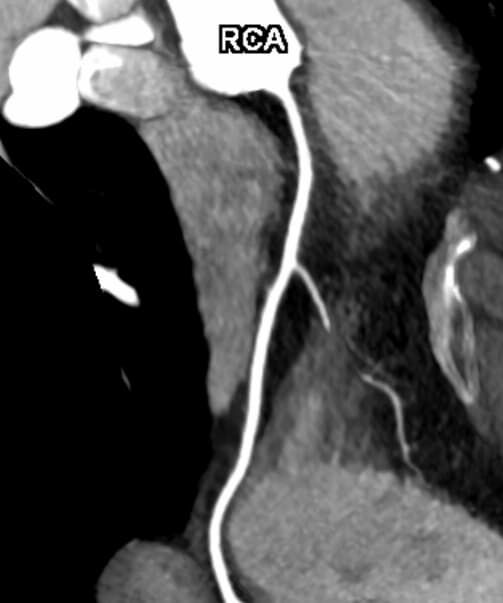

• Darstellung der Blutgefäße (sog. CT- Angiographie)

Herz

• Darstellung der großen Gefäße zur Erkennung von Gefäßverschlüssen (z. B. Mesenterial - Arterienembolie oder Einengungen von Gefäßen (z. B. Nierenarterien)

• Darstellung und Therapieplanung von Aneurysmen (CT- Angiographie)

• mehrdimensionale Darstellung vasculärer Strukturen mit zahlreichen Auswertungstools